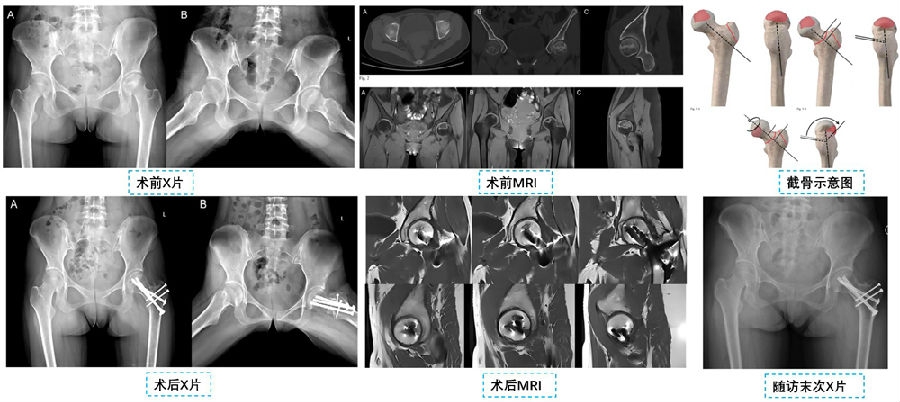

2023年,解放军总医院张洪、罗殿中教授团队[19]在JBJS杂志上报道了一名股骨头坏死患者的成功保髋的病例(图10)。该患者通过股骨颈基底旋转截骨术,将股骨头的坏死区域旋转出承重区,并实现了坏死区域的完全修复。另一项研究由Edmond等人[20]进行,作者报道了一种改良的“灯泡”技术,通过股骨头-颈部交界处的窗口对股骨头进行减压,从而提供了直接进入骨坏死病变的通道。Lu等人提出了一种β-磷酸三钙生物陶瓷(β-TCP)系统 ,用于治疗ONFH,通过促进血运重建和骨再生来提高治疗效果。

图10. 股骨颈基底旋转截骨术后成功保髋(引自JBJS Case Connector 13(4):e23.00431)